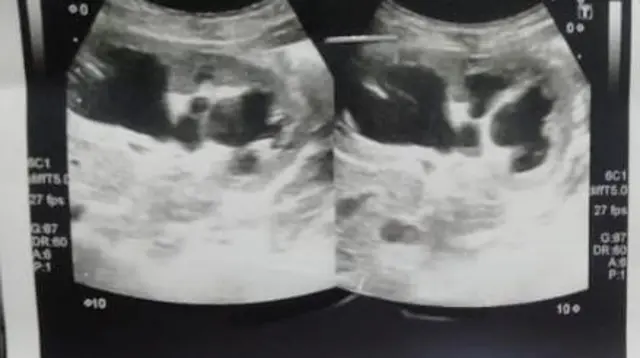

ڈاکٹر مشتاق احمد نے بی بی سی سے بات کرتے ہوئے بتایا کہ جب انھوں نے بچی کا معائنہ کیا تو ’مجھے پیٹ میں رسولی اور پانی کی تھیلی محسوس ہوئی۔ میں نے الٹرا ساوئنڈ کروایا تو اس کی تصدیق ہوئی۔‘

پروفیسر ندیم اختر کے مطابق ’ایک وجہ یہ بھی ہے کہ ایسے کیسز میں الٹرا ساوئنڈ، سی ٹی سکین اور ایم آر آئی کروا کر دیکھنا ضروری ہوتا ہے کہ پیٹ میں کیا مسئلہ ہے۔‘